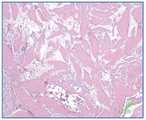

도 10은 본 발명의 일부 구체예에 따라 골 조성물 임플란트에 대한 생체내 골 섬유 간격, 세포충실성, 및 골모세포원성 분화를 예시한다.